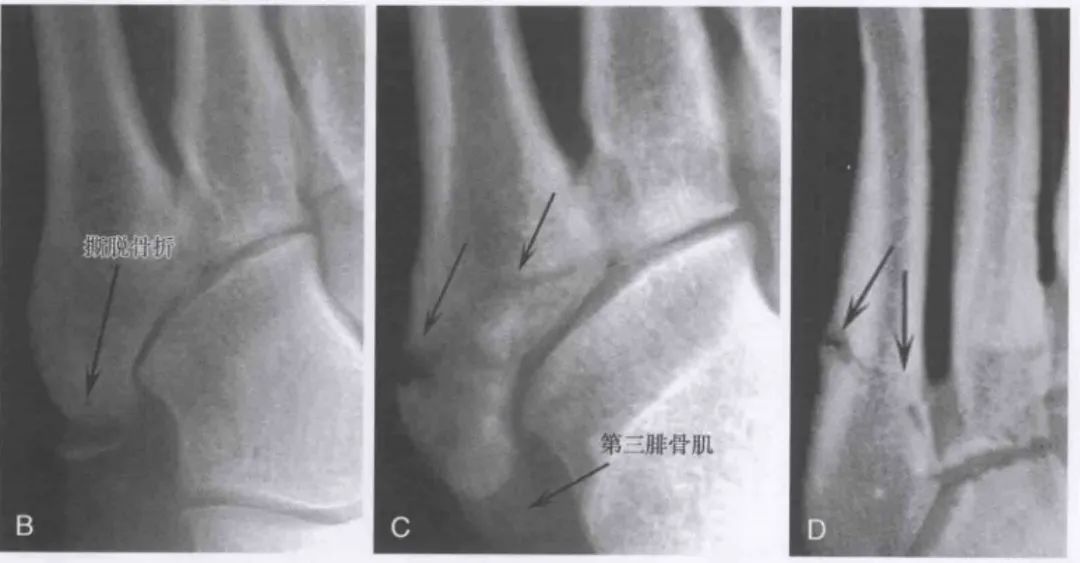

箭头显示第 5 跖骨基底骨折;B. 移位的跖骨结节骨折 (I 区);C. 移位的干骺端骨折(II 区);D. 骨干的应力性骨折(III 区)。图源:文献:doi:10.1530/EOR-21-0025

Dameron 和 Quill 提出把第 5 跖骨基底部分的骨折分为为三个区域:第 5 跖骨骨折分区分型,图源:《坎贝尔骨科手术学》I 区:为第 5 跖骨基底结节部的骨折,常为撕脱骨折,也称为假 Jones 骨折;II 区:为第 5 跖骨基底干骺端骨折,骨折常为横形,又被称为 Jones 骨折。通常累及第 4-5 跖间关节,由于干骺部血供较差,Jones 骨折不愈合的发生率较高;III 区:为干骺端以远 1.5 cm 近端骨干的骨折,常为应力骨折。该处骨折的特点是移位较少,但不易愈合,容易发生再骨折,不愈合率可达 66.7%。